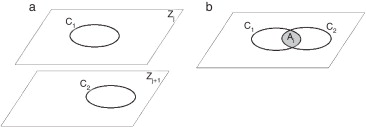

Axioma 1: Dos contornos, en planos consecutivos (fig. 1 a), pertenecen a una misma isosuperficie (estructura anatómica), si se cumple con (6):

|

( 6) |

donde Ai es el valor del área de intersección entre estos (fig. 1 b), A1, A2 son las áreas de los contornos y t es el valor permisible. La selección del valor de t está en función de la distancia entre cortes, la región anatómica de análisis y la experiencia adquirida por el especialista.

|

|

|

Figura 1. a) Contornos en planos consecutivos. b) Proyección ortogonal del contorno C1,Zj en el plano Zj+1 y determinación del área de intersección con C2,Zj+1 . |

El proceso consiste en aplicar el axioma 1 a la totalidad de los contornos. Se consideran 3 escenarios posibles: 1) si la relación entre las áreas es mayor o igual a t , entonces (Ck,Zj , Ck,Zj+1 ) forman parte de una misma isosuperficie; en caso contrario, 2) (Ck,Zj , Ck,Zj+1 ) no pertenecen a la misma isosuperficie; 3) si Ck,Zj no tiene relación con ningún contorno del plano Zj+1 , entonces Ck,Zj se considera información no válida y es descartado. Una vez finalizado este proceso, se tiene una lista donde cada elemento representa una isosuperficie, y dentro de esta los contornos que la conforman.